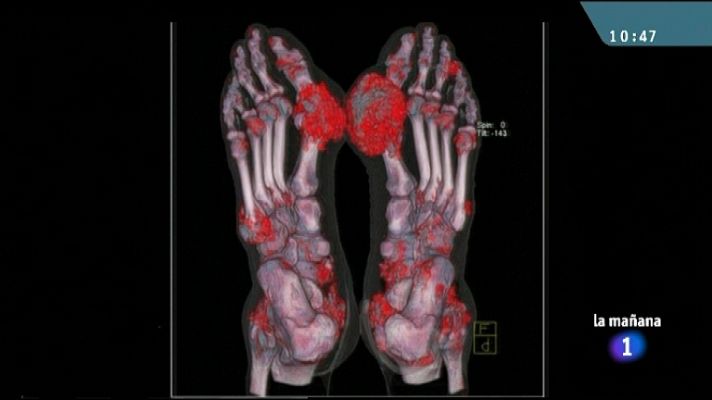

Ácido úrico al final del año

Ácido úrico al final del año